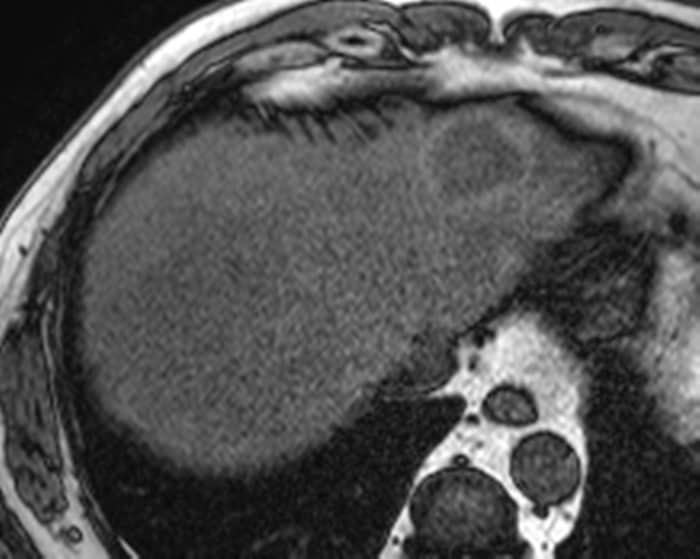

Ung thư đường mật - Ảnh 3

Ung thư đường mật

» Thông tin: Nam giới – 57 tuổi.

» Lâm sàng: Đau bụng.